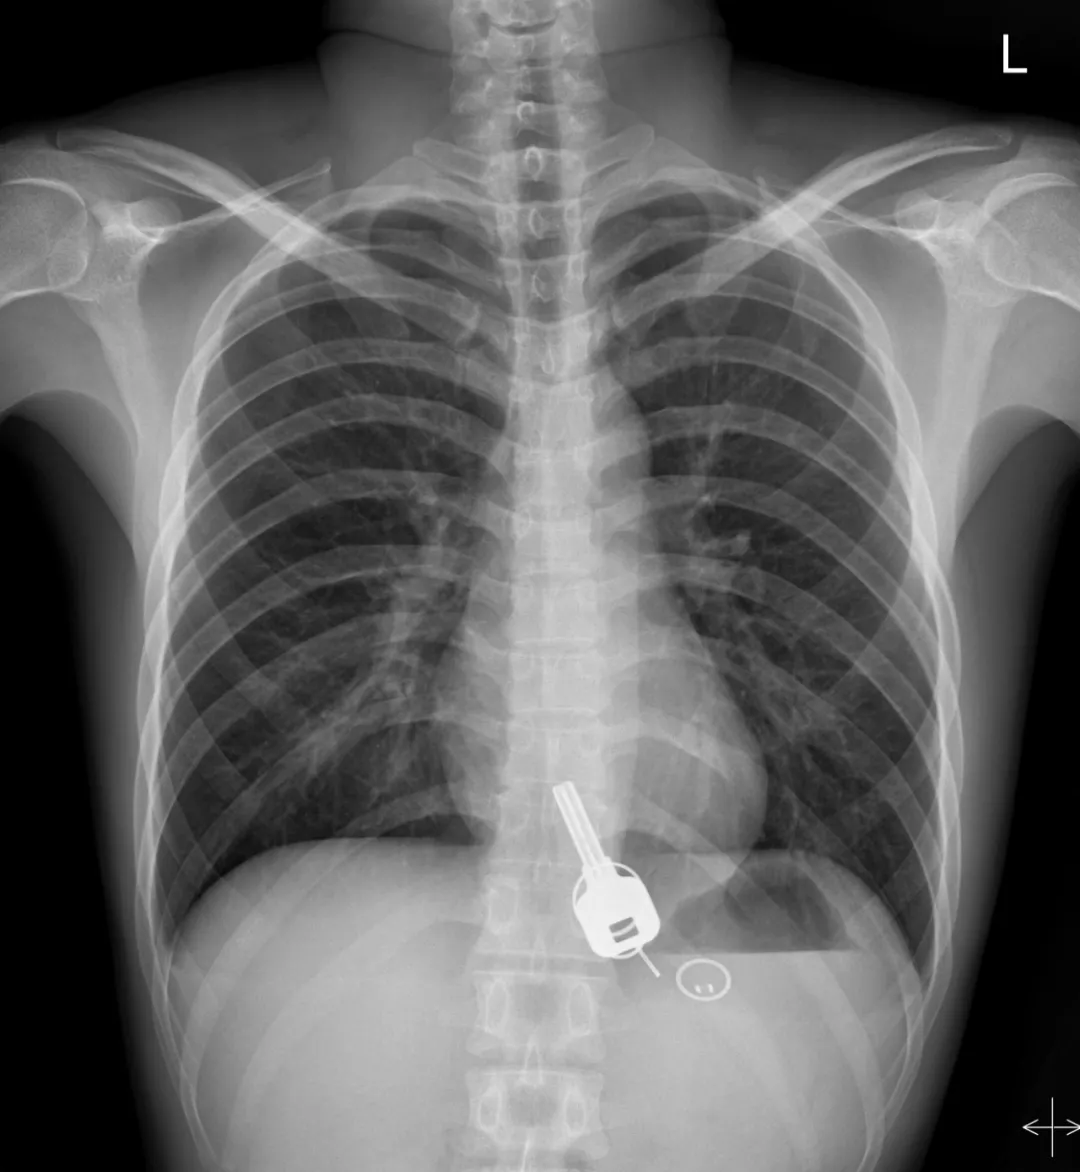

而下面東莞小哥喝酒喝到吞鑰匙

廣東東莞的常先生酒后回家找不到鑰匙,酒醒后他感到胸口疼痛,去醫(yī)院一查,發(fā)現(xiàn)一把鐵鑰匙、2個(gè)鑰匙扣、1個(gè)門禁牌清楚顯示在肚子胃區(qū)的位置上。

醫(yī)生準(zhǔn)備在胃鏡下取出鑰匙,不料,因鑰匙太大在常先生喉嚨附近食管入口處卡住了,取不出來,最后,醫(yī)生決定給常先生做無痛胃鏡,麻醉后,常先生食管入口處肌肉松弛,鑰匙終于順利取出!。